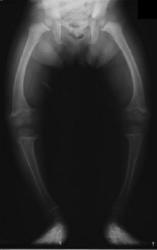

X-ray showing malformation of the legs caused by rickets

Rickets is a softening of the bones which can lead to fractures and deformity. It was prevalent in Victorian times and although largely eradicated in the West it is still one of the most frequent childhood diseases in many developing countries.